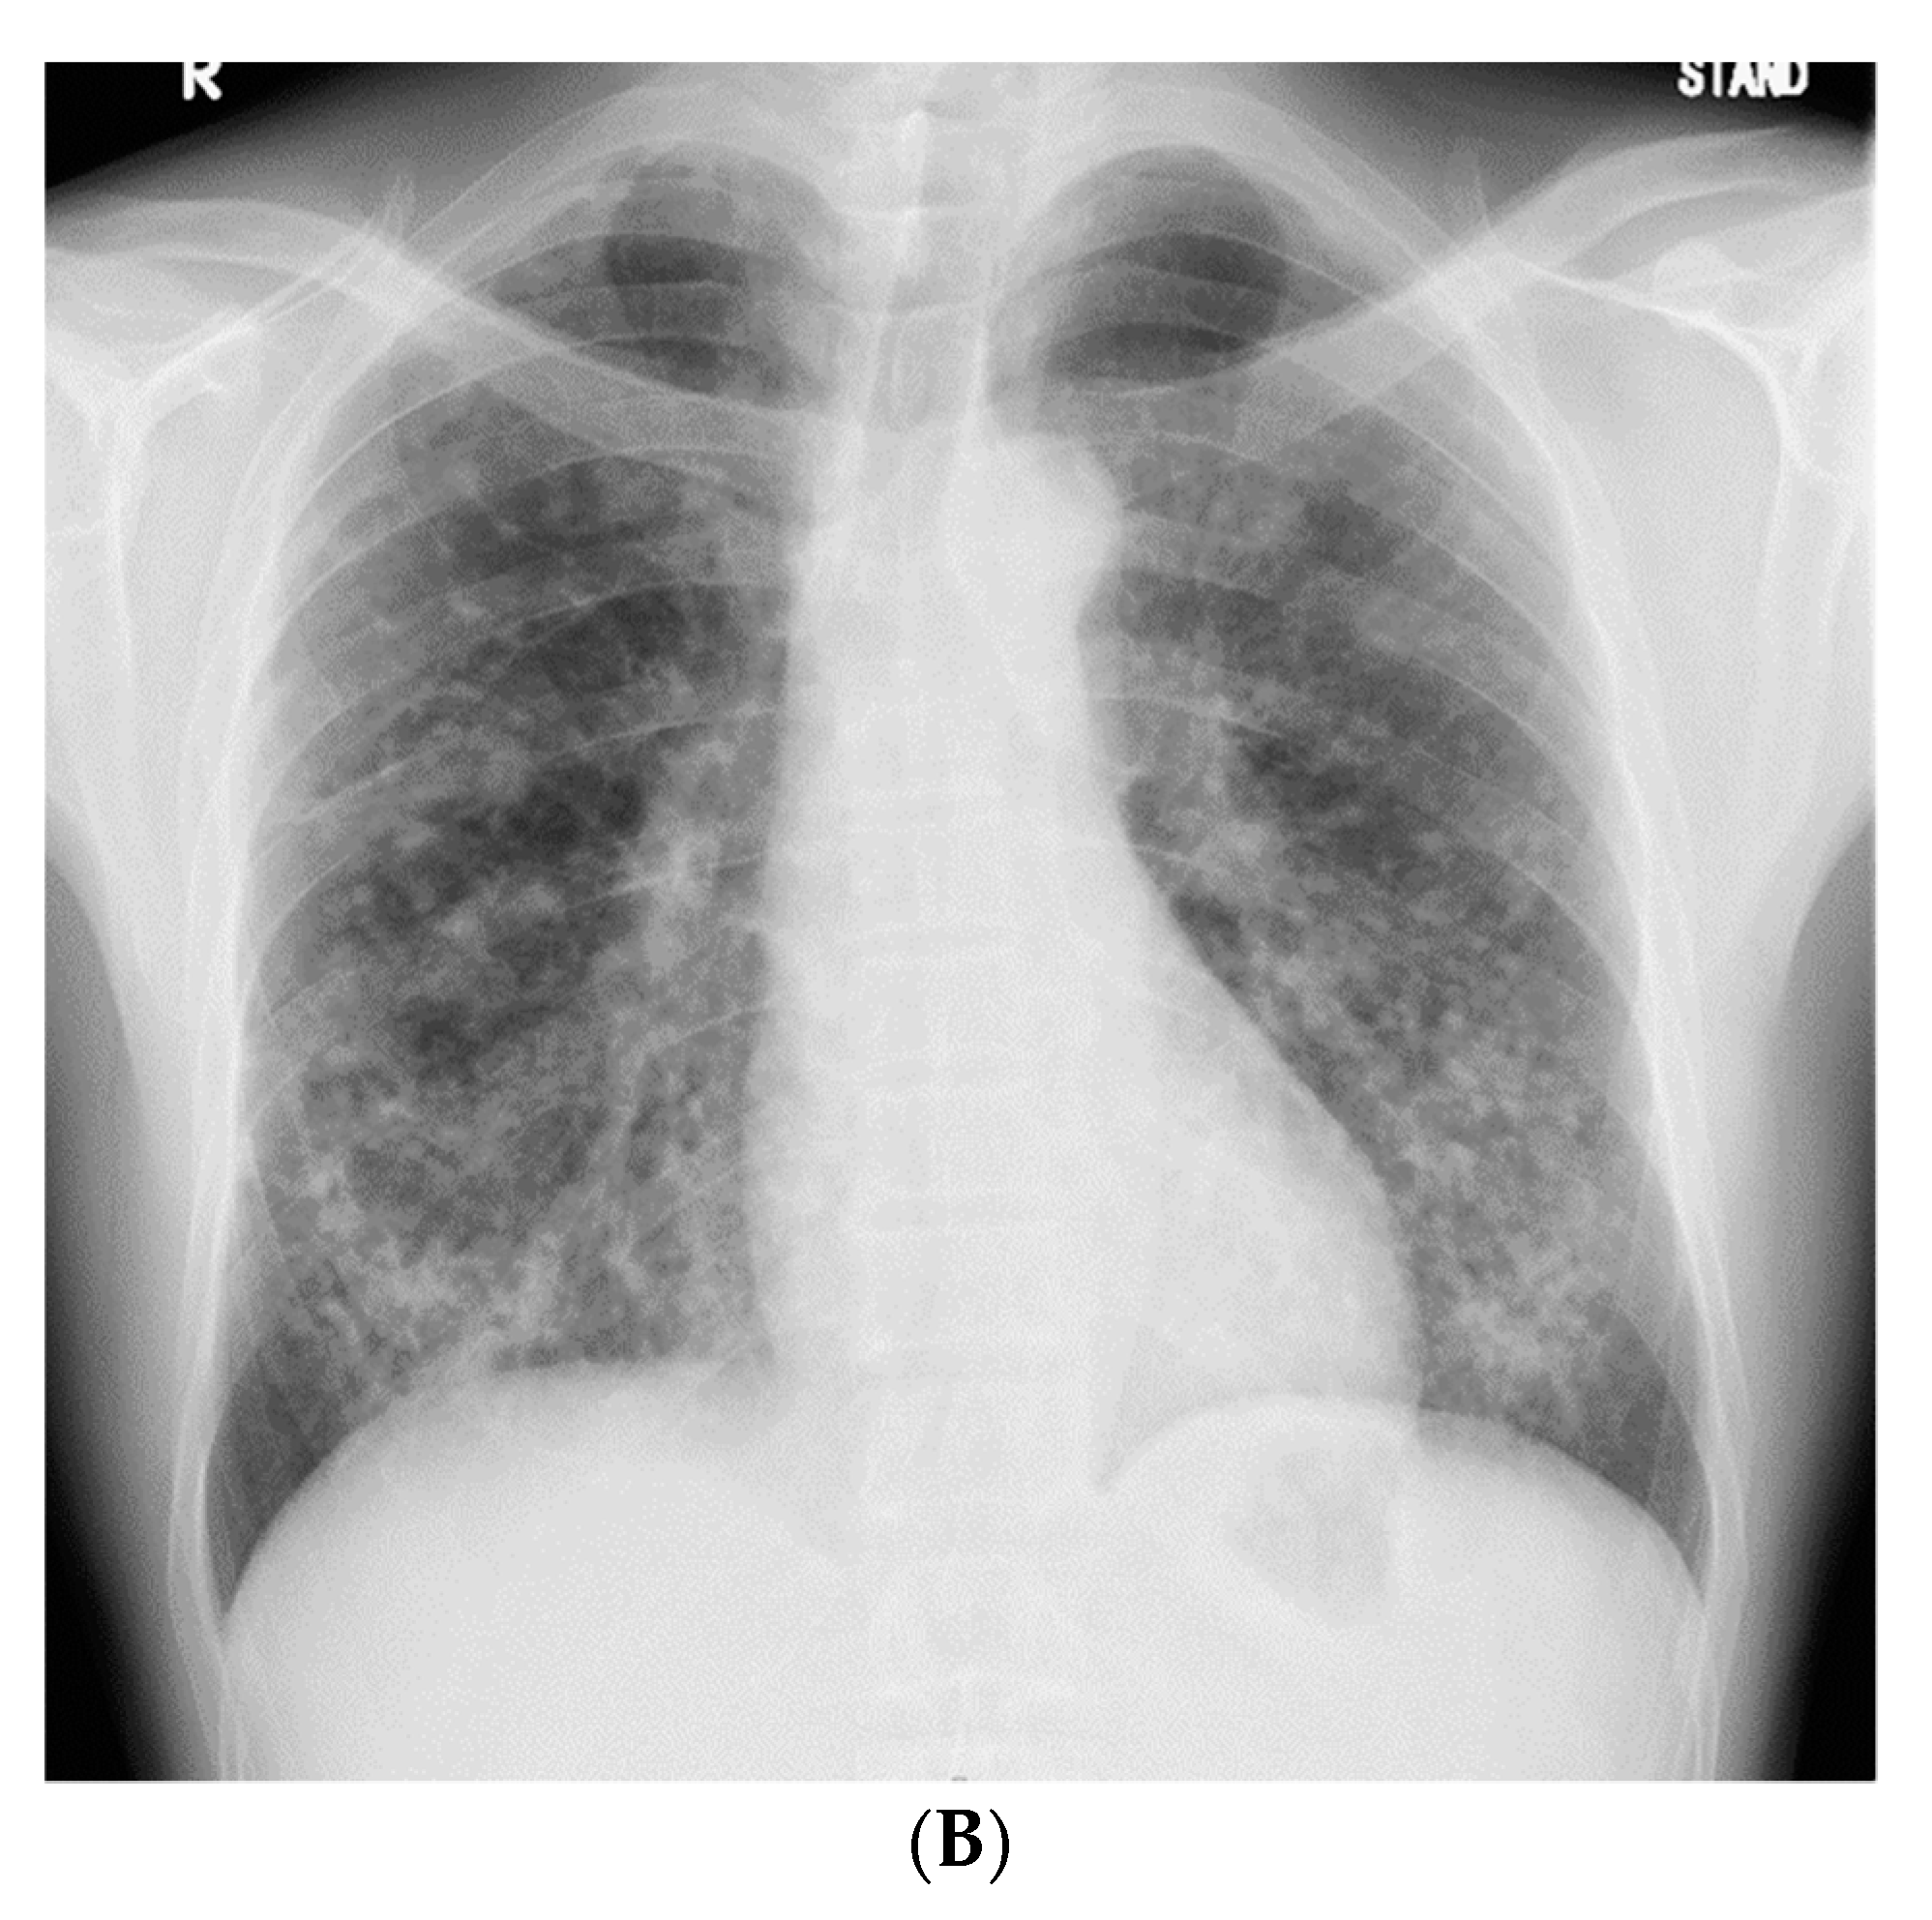

2. Case Presentation